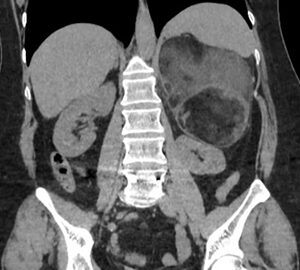

Agosto 2025. Sanatorio de la Cañada

Pte femenino de 52 años, Mc: dolor abdominal difuso, App: hta, Mh: Losartan, A qx: osteosíntesis lumbar.